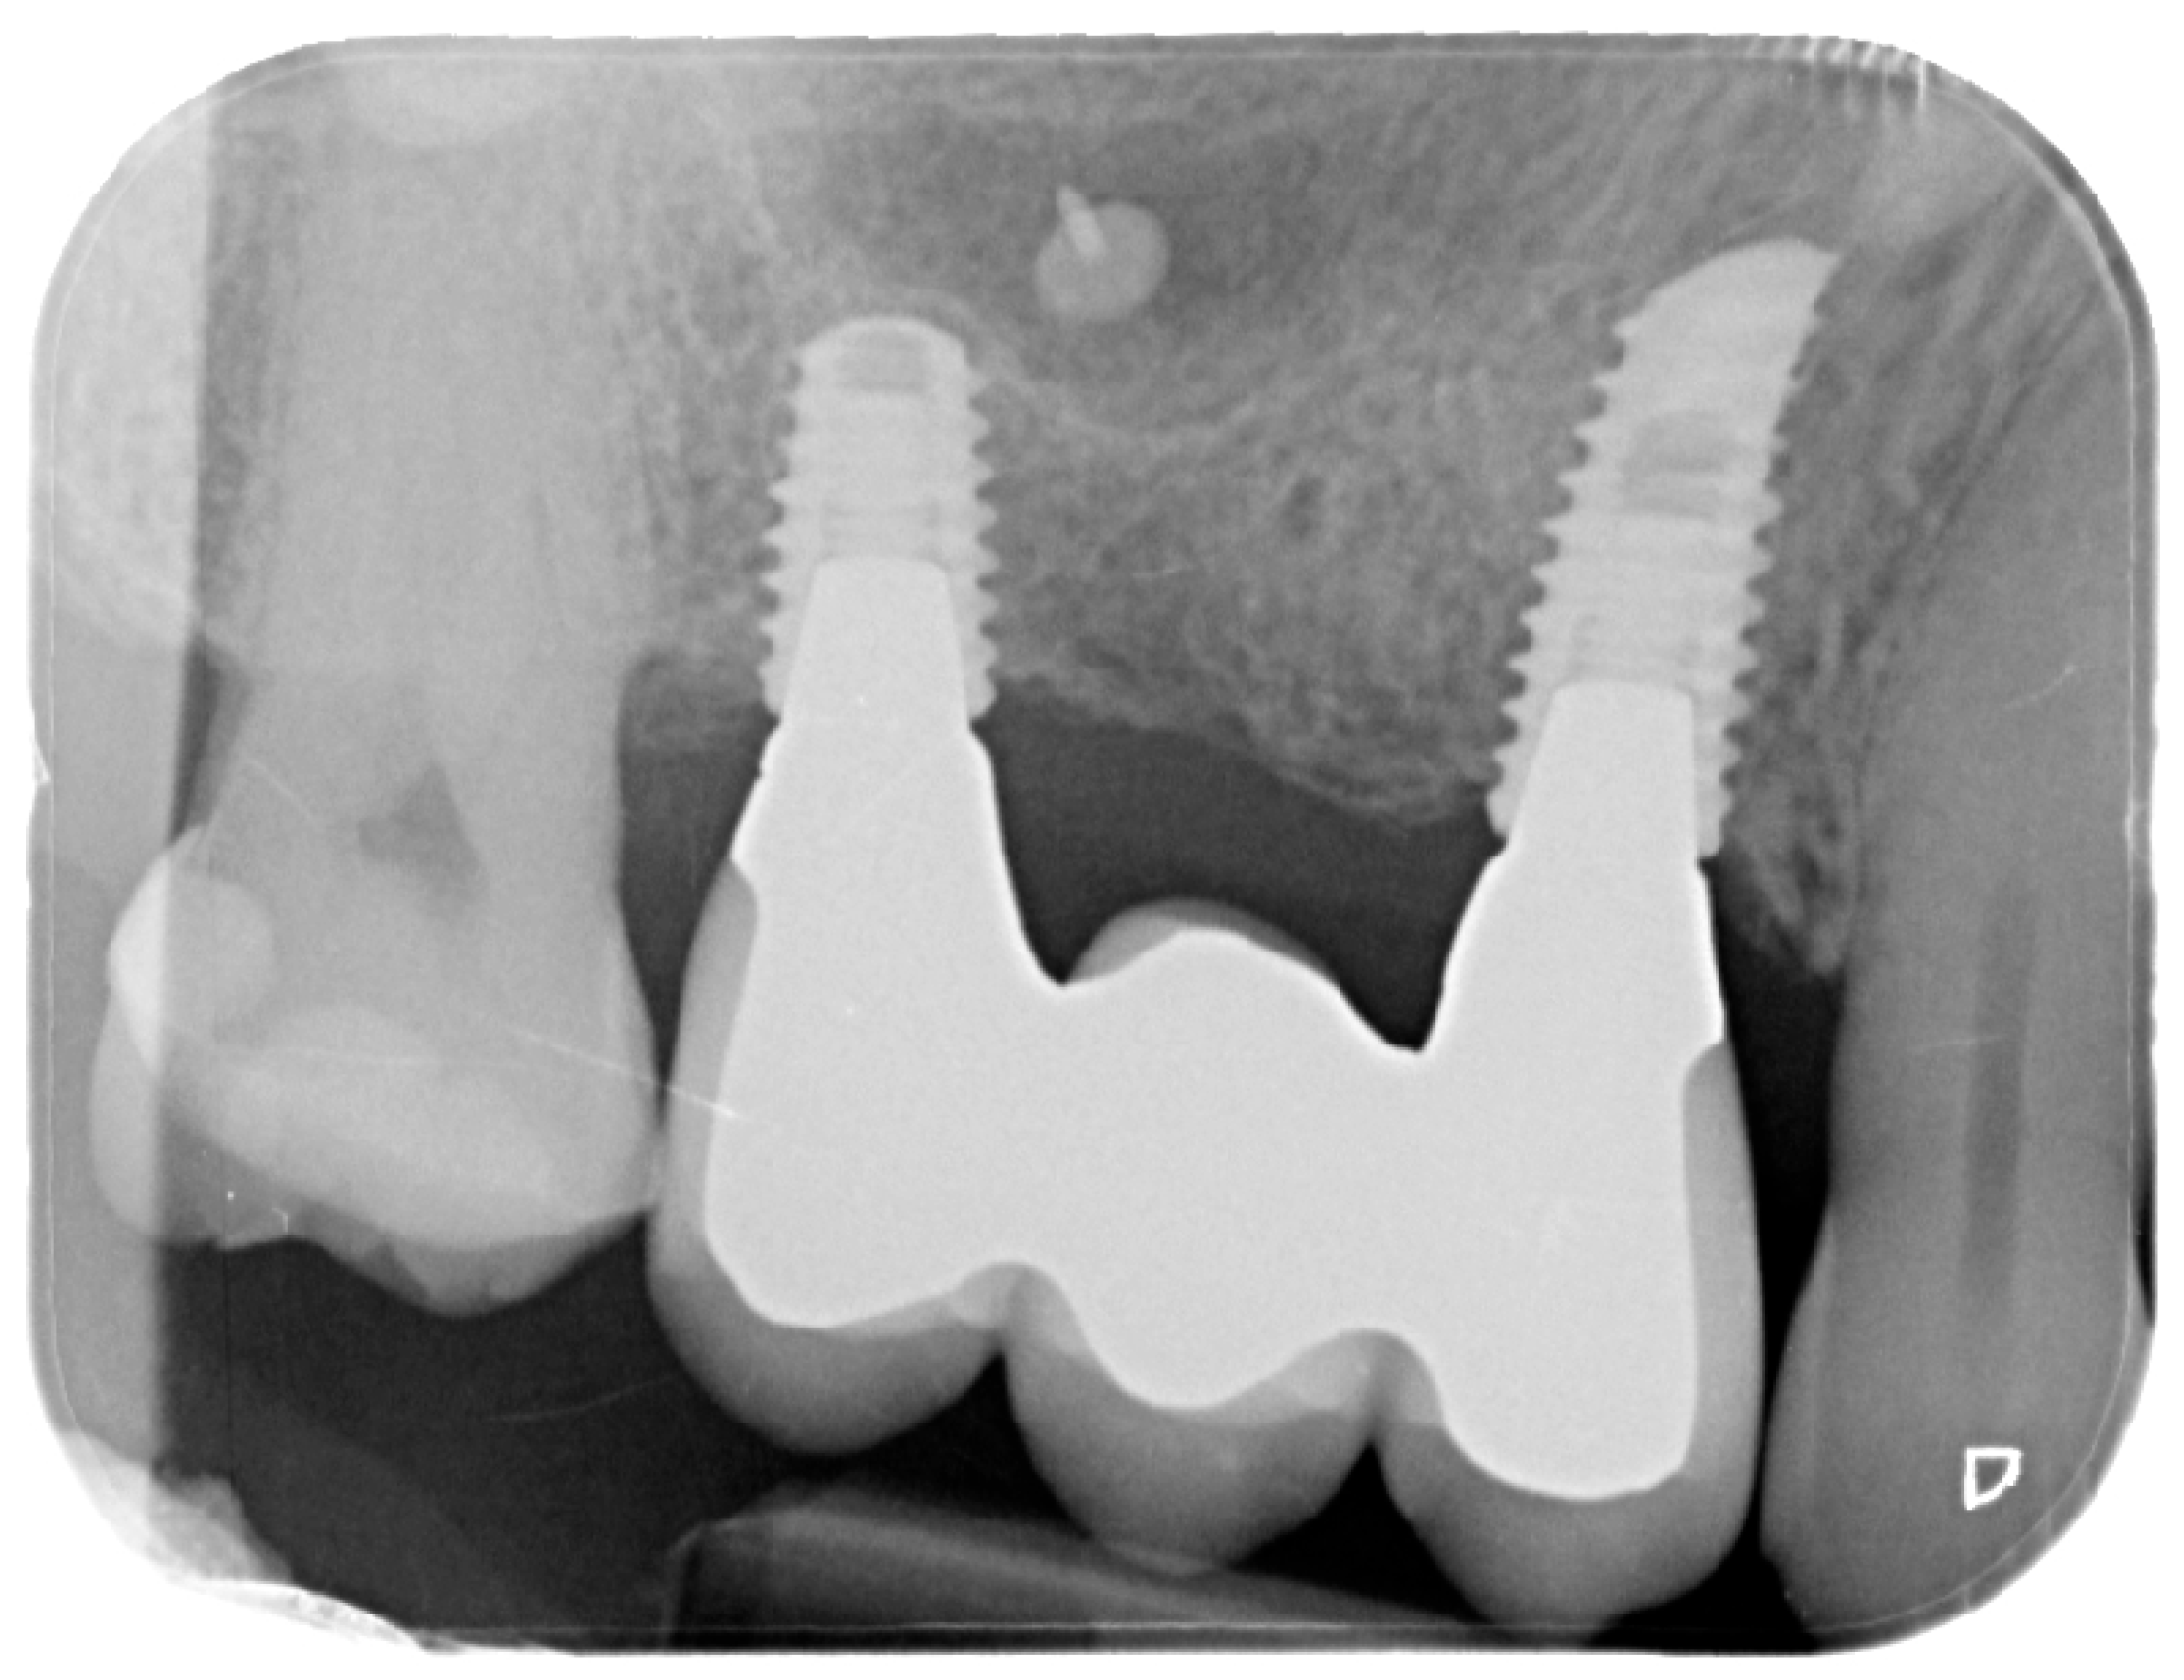

Healing abutments were screwed to the implants and the flaps were sutured. Additional peri-implant plastic surgery procedures (connective tissue grafts or free gingival grafts) were performed when needed in order to have at least 2 mm of attached keratinized mucosa. The prosthetic phases began upon healing of the soft tissues, and definitive screw-retained prostheses were finally delivered (Figure 11, Figure 12 and Figure 13).

Figure 12. Intraoral X-ray at delivery of the final prosthesis.

Medicina 61 01814 g012

Figure 13. Intraoral X-ray at one year follow-up.